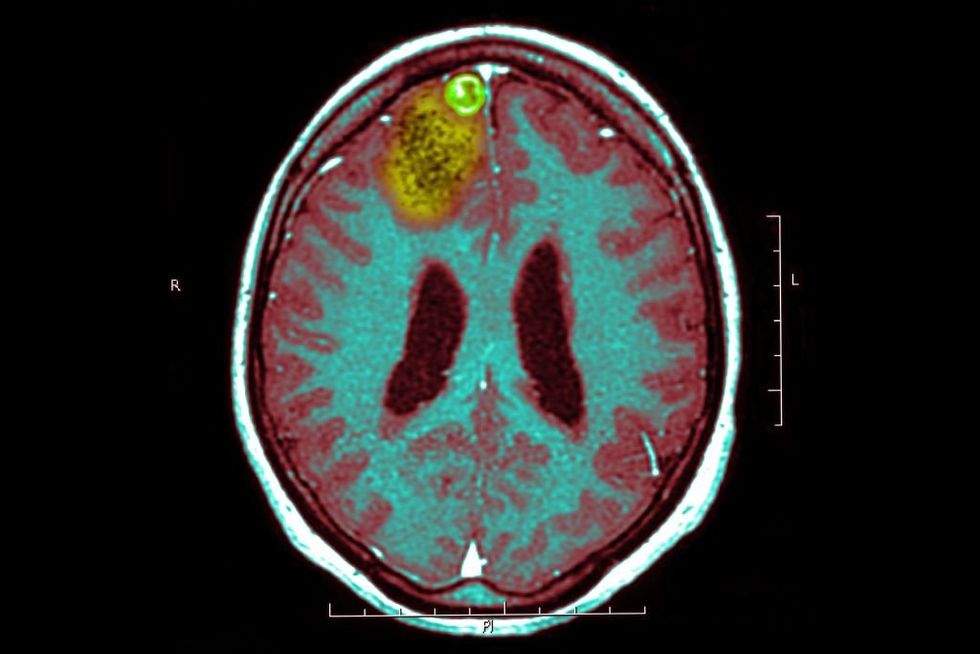

'I don't want to die': Doctor facing certain death from brain cancer tries friend's experimental treatment – which shows promise

A leading skin cancer doctor is hopeful that an experimental treatment will bring a miracle and cure his nearly uncurbable brain cancer. Richard Scolyer is a professor at Sydney University in Australia and a surgical pathologist. Professor Scolyer is also suffering from one of the deadliest forms of cancer – a glioblastoma.The Mayo Clinic defines a glioblastoma as:A type of cancer that starts as a growth of cells in the brain or spinal cord. It grows quickly and can invade and destroy healthy tissue. Glioblastoma forms from cells called astrocytes that support nerve cells. Glioblastoma can happen at any age. But it tends to occur more often in older adults and more often in men. Glioblastoma symptoms include headaches that keep getting worse‚ nausea and vomiting‚ blurred or double vision‚ and seizures.According to Healthline‚ "The median survival time for adults with glioblastoma is 15 months."Just 3% to 5% of patients survive more than three years.Scolyer – a 57-year-old married father with three children – was diagnosed with brain cancer last June. For a treatment strategy‚ Scolyer turned to Georgina Long – his friend and co-director of the Melanoma Institute Australia.According to the Australian Broadcasting Corporation‚ "Both have been at the forefront of groundbreaking advances in melanoma treatment and saved thousands of lives with their immunotherapy approach.""We've taken everything‚ absolutely every bit of knowledge … that we've pioneered in melanoma and we've thrown it at Richard's tumor‚" Long told the outlet. Knowing the extraordinary odds and that timing is critical‚ Long proposed a radical plan to try to cure the nearly incurable brain cancer. However‚ there were significant risks. Professor Scolyer was the first in the world to delay brain surgery to remove the tumor and start with pre-surgery combination immunotherapy."Combination immunotherapy counters several immunosuppressive elements in the tumor microenvironment and activates multiple steps of the cancer-immunity cycle‚" according to the National Library of Medicine. The professor is also the first person to receive a personalized vaccine to combat the tumor."Brain cancer doctors were so worried this would kill me quicker or result in terrible side effects‚" Scolyer explained.Scolyer joked that the treatment plan was a "no-brainer.""It's not a hard decision to make when you're faced with certain death. I'm more than happy to be the guinea pig to do this‚" Scolyer said.Scolyer‚ his family‚ and the treatment team were extremely nervous when it came time for his recent brain scan at the end of January. Long said her friend's brain is "normalizing"A "thrilled" Scoyler said there's "no recurrence of my supposedly incurable glioblastoma!" See on Instagram Scolyer said the chance that he is cured of his aggressive cancer is "miniscule‚" but he's optimistic that "a miracle could happen."Scolyer proclaimed‚ "I'm confident‚ to be honest‚ that it's going to make a difference for future brain cancer patients."He cautioned‚ "I'm just one patient though. We won't really know [it works] until we do clinical trials."Scolyer told the BBC that he wants to live long enough to see his kids "become truly independent."The doctor said that he is "extraordinarily resilient‚" but "it's tough.""I love my family. I love my wife… I like my work‚" he declared with a grimace."I'm pissed off. I'm devastated‚" he said. "I don't want to die."His only comfort is that the data from his experimental treatment is "changing the field‚ and if I die tomorrow with that‚ I'm very proud."Like Blaze News? Bypass the censors‚ sign up for our newsletters‚ and get stories like this direct to your inbox. Sign up here! An experimental treatment against 'certain death' | Professor Richard Scolyer | Australian Story www.youtube.com